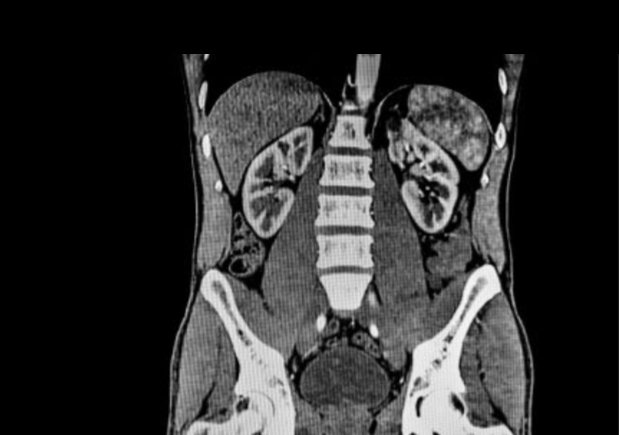

2- الأشعة المقطعية (CT-Scan):

- اكثر دقة من الأشعة السينية.

- تأخذ صورة ثلاثية الأبعاد (3D).

- تستخدم في تشخيص الحالات المرضية في

الأعضاء والأنسجة والعظام.

- تلتقط الصور بزاوية 360 درجة.

- أكثر شمولية من الأشعة السينية.

- الإشعاع أعلى من الاشعه السينية بأضعاف.